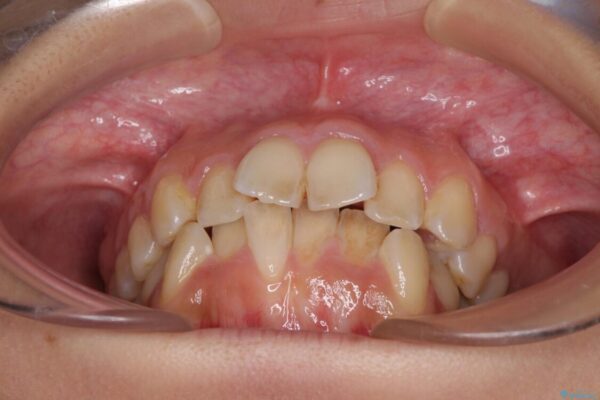

前歯のデコボコと上顎の前突感による口の閉じにくさを気にして来院された患者様です。

目立たない装置を希望されたので、上顎が裏側装置のハーフリンガルを選択し、上下左右の小臼歯(計4歯)を抜歯して矯正治療を行うこととしました。

治療前

• デコボコと口元の突出感 ハーフリンガルでの抜歯矯正 治療前画像